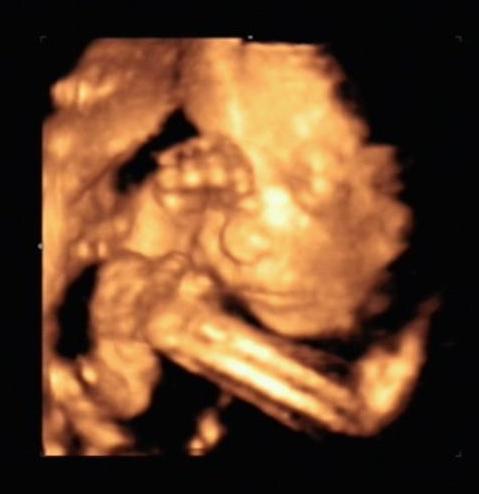

a 7ik héttől már látható a szívcső lüktetése, 8ik héttől a gerincoszlop és már akár testmozgások is láthatók! Ez nem jelenti azt, hogy feltétlenül mozogni is fog az uh alatt, valamikor ő is pihen!

Persze ezekhez szakértő szem szükséges, tehát az orvos mindent látni fog, és el fog mondani!!